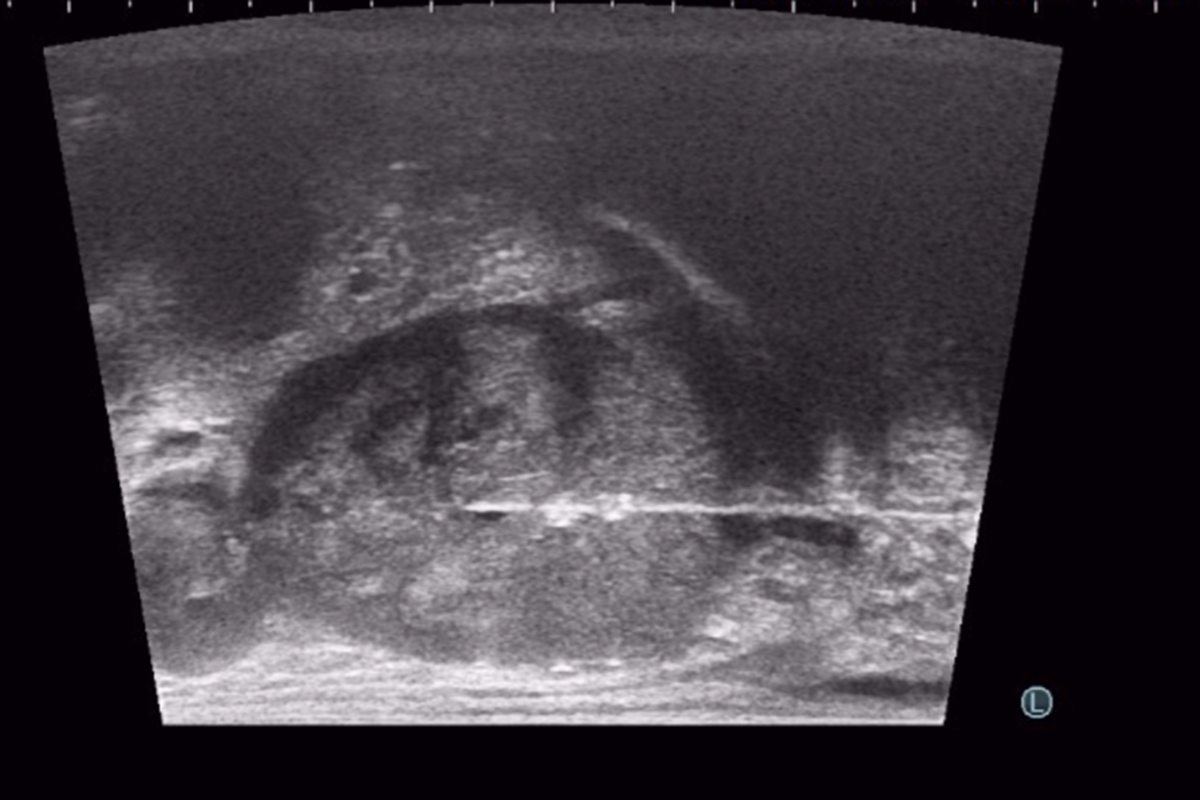

TP prostat biyopsisi, yani temiz prostat biyopsisi, hastanın isteğine göre, lokal uyuşturma ile, ya da kolonoskopideki gibi sedasyon dediğimiz hafif uyutma ile yapılabilir.  TRSU biyopsiden farklı olarak, temiz prostat biyopsisinde hastaya sedyeye sırtüstü yatırılır ve bacakları iki yana-yukarı doğru açılır. Biyopsi sırasında iğne makattan geçmez, ama ultrason görüntüsü almak için yine makata ince bir ultrason başlığı yerleştirilir.  Doktor, kaydırıcı ve uyuşturucu özellikleri olan bir jeli hastanın makat bölgesine sürer. Daha sonra, prob adı verilen ince ultrason başlığını yavaş bir şekilde hastanın makat bölgesine yerleştirir. Hastamız kendisini gevşek bırakır ve makat bölgesini sıkmazsa, başlık hiç rahatsızlık vermeden, yumuşak bir şekilde içeri doğru ilerler. Kendisini sıkan hastalarda bile, zorlama yapılmadan yavaş davranılırsa, makat girişi bir süre sonra gevşeyerek başlığın acısız bir şekilde girmesine izin vermektedir. Çok nadiren (yaklaşık %1), makat girişinde darlık ya da yarası olan hastalarda bu aşamada ağrı olabilir. Bu durumda hastanın canını acıtarak işleme devam etmeyiz. İşlem hasta uyutularak, anestezi altında yapılır.

Başlığı makat bölgesine yerleştirdikten sonra, Ultrason’da prostat, TRUS biyopsi ultrason cihazından daha da net  bir şekilde görülür. Bundan sonra, çok ince bir iğneyle perine adı verilen, makat ile yumurtalıklar arasındaki cilt bölgesine uyuşturucu ilaç verilir. Cilt uyuştuktan sonra aynı ince iğne daha içeri doğru ilerlenip, prostatın çevresine de uyuşturucu ilaç (lokal anestezi) yapılır. Böylece giriş alanı ve prostatın tamamı uyuşur ve işlemin bundan sonraki kısmını hasta en fazla sinek ısırığı gibi hafif bir acı olarak hisseder. Bu aşamada, ülkemizde çok az merkezde uygulanan, koaksiyel iğne ile biyopsi işlemini yapmaktayız. Ülkemizde birçok merkezde TP prostat biyopsisi yapılmaktadır. Ancak çoğunda, prostattan alınacak her parça için iğne perine adı verdiğimiz bölgeye tekrar tekrar girip çıkmaktadır. Bu da hem hastaya ağrı vermekte, hem de yan etki risklerini arttırmaktadır. Bu yöntemle yapılan TP biyopsi işlemleri ağrılı olduğu için hastanın uyutulması gerekmekte, bu da işlemin ücretini ve süresini arttırmakta ve anestezinin ek yan risklerini getirmektedir. Bizim uyguladığımız tek iğne yönteminde ise, koaksiyel iğne adı verilen bir iğne, uyuşturucu yapıldıktan sonra perinenin bir tarafından içeri yerleştirilir. Bundan sonraki parçalar, biyopsi iğnesi bu koaksiyel iğnenin içinden geçirilerek alınır. Böylece, ciltten sadece tek bir iğne girişi ile, prostatın bir tarafındaki tüm parçalar alınabilir. Bu yöntemde iğne ağrısı olmadığından, lokal anestezi ile uygulanmaktadır. Prostatın diğer tarafı için de tek bir iğne girişi kullanılır. Böylece, sadece iki iğne girişi ile, prostatın tamamından istediğimiz sayıda parça alabilmekteyiz. Temiz biyopsi işlemi yaklaşık 20 dakika kadar sürer ve yukarıda da bahsettiğimiz gibi, hastamız çok az ağrı hissederek işlemi tamamlar.